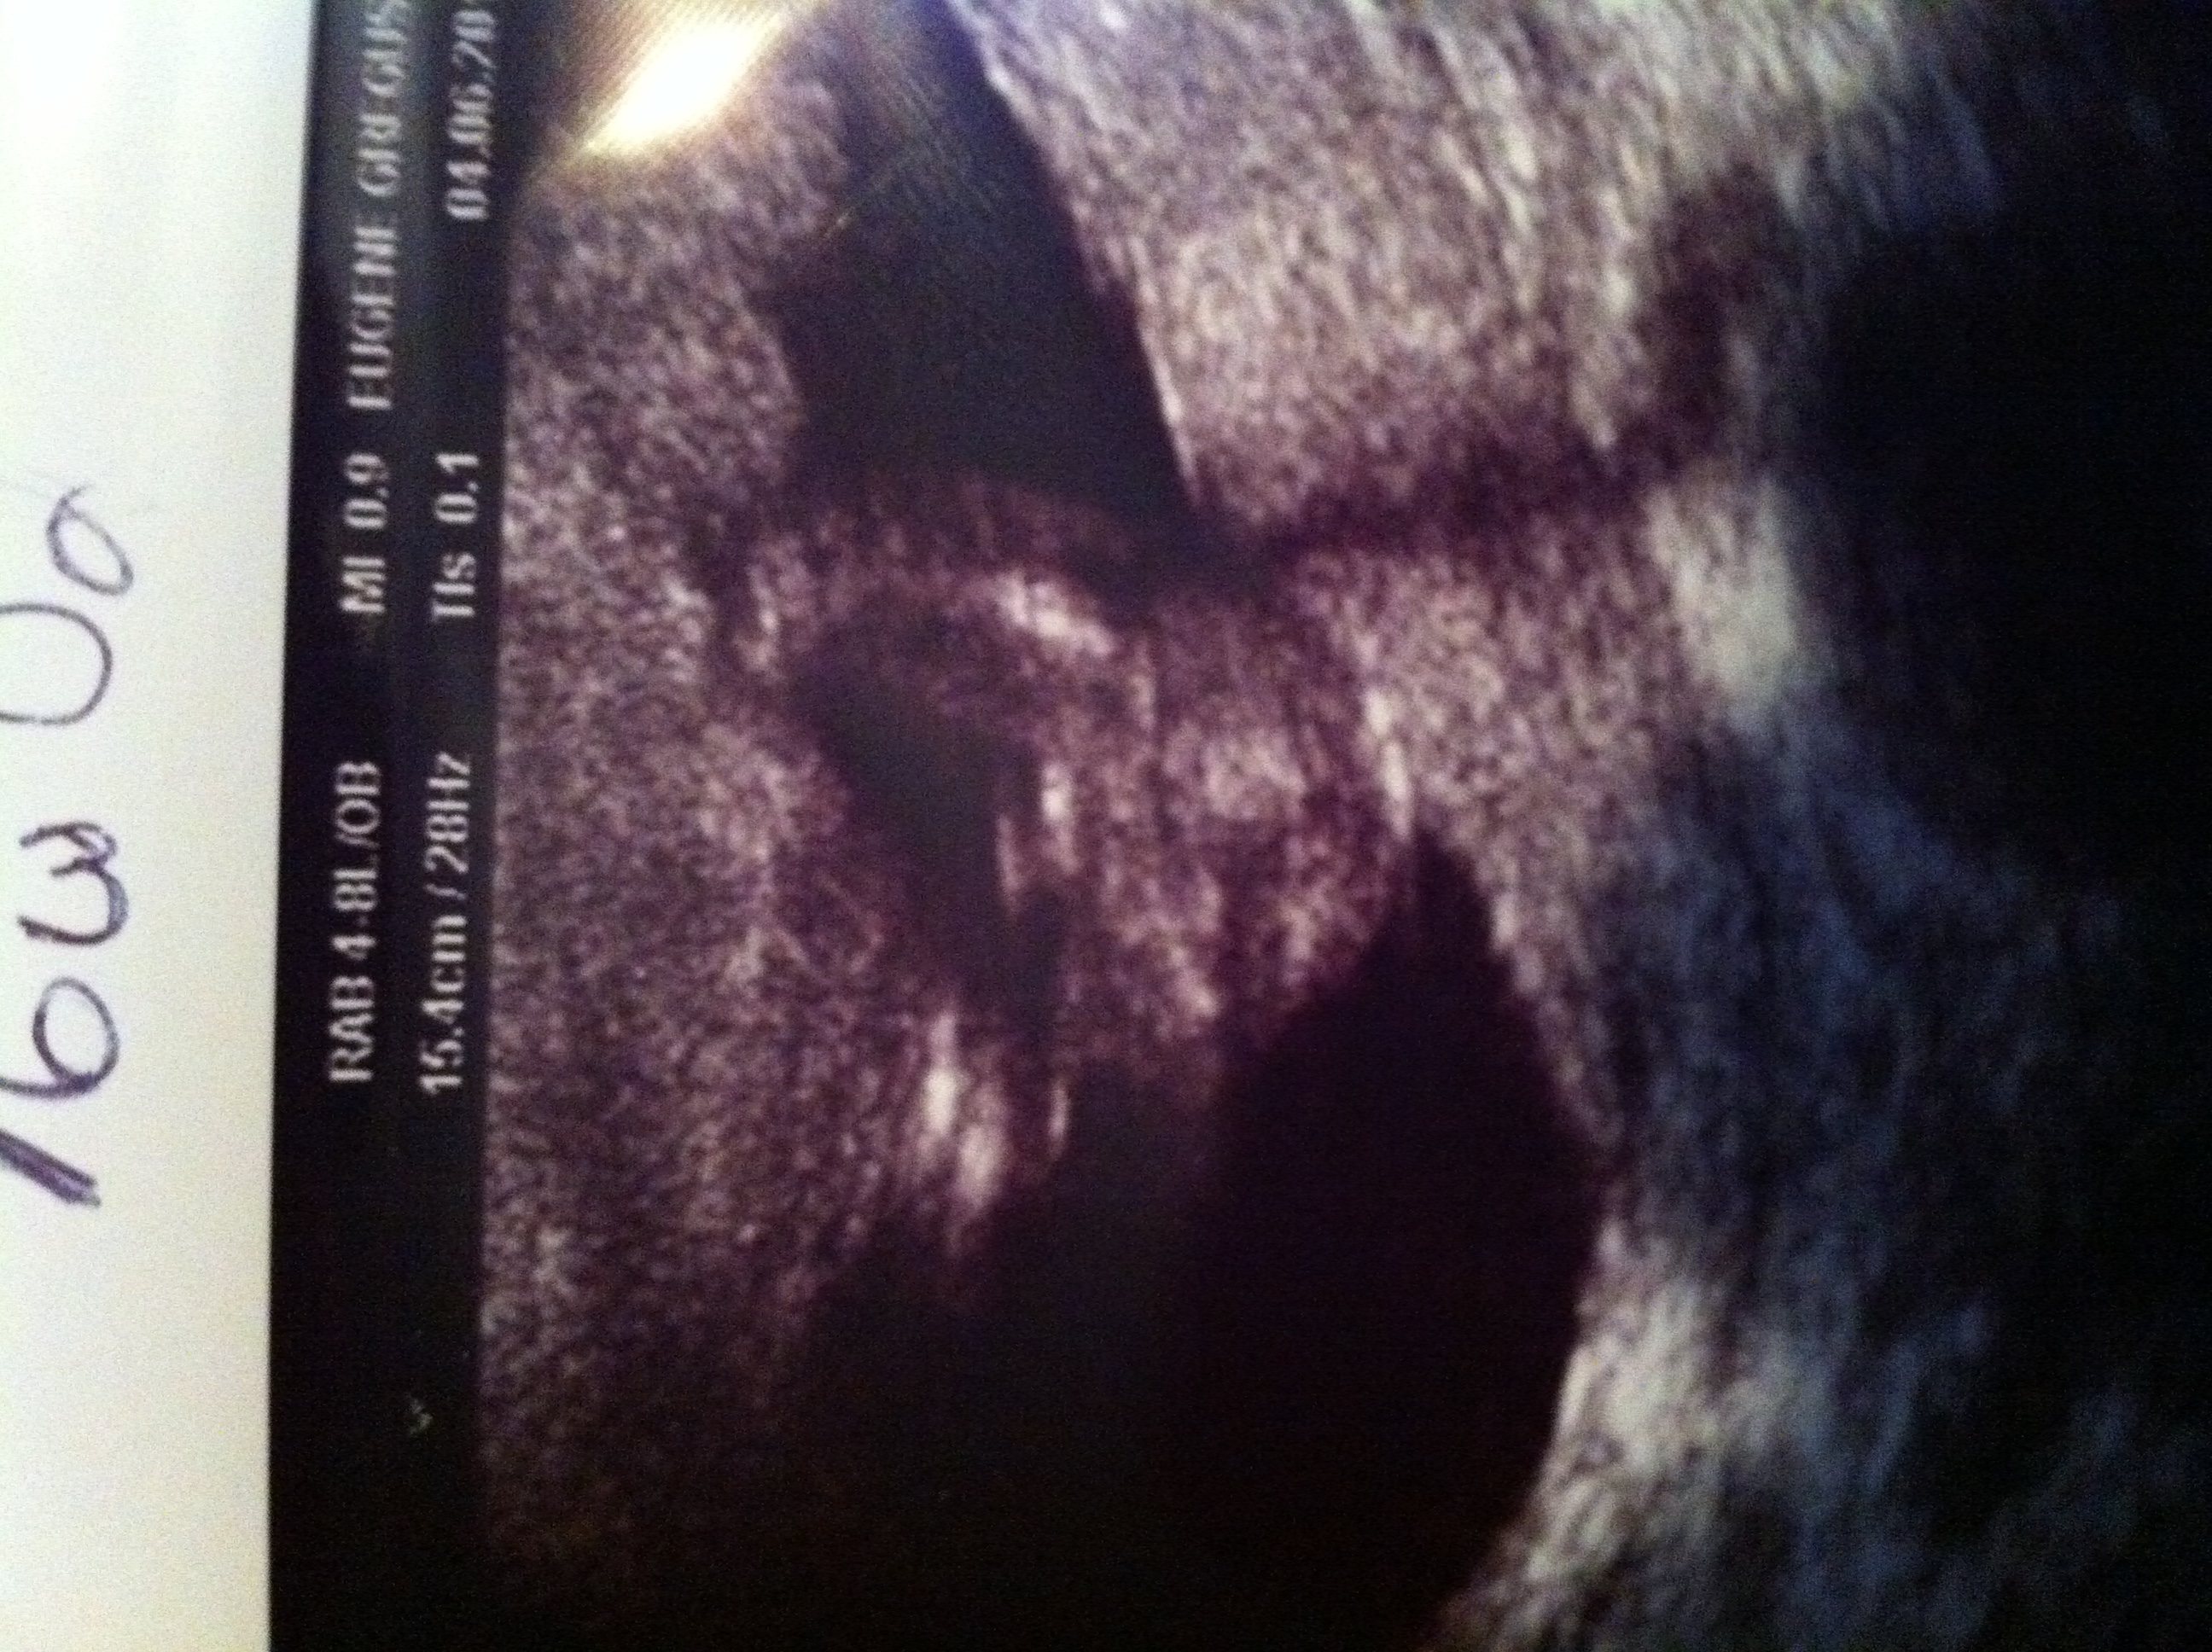

Blood DNA test said we were having a girl. At our 16week ultrasound the doctor could not confirm if it was a boy or girl. Comments? Will post both pictures that I have.Attachment 11654

Looks like a boy to me. Unless the blood test was the MaterniT21 then I wouldn't put much stock in it. Congrats!

That looks like a boy!!

That's a boy.

Def looks to be a boy!

That's clearly a boy, congratulations xxx